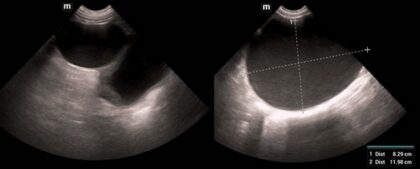

Dieses vetinar richtet sich an Tierärzt:innen, die ihre Kenntnisse in der Andrologie des Hundes praxisorientiert auffrischen möchten. Anhand vielfältiger realer Fallbeispiele aus der Klinik beschäftigen wir uns mit der Pathologie und dem klinischen Erscheinungsbild sowie unseren diagnostischen Möglichkeiten und Therapieoptionen bei verschiedenen Erkrankungen des Genitaltrakts beim Rüden.